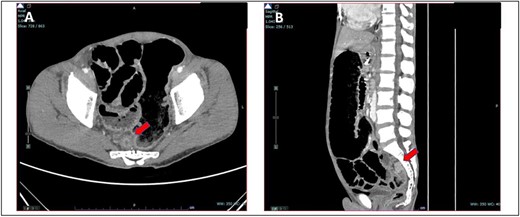

A 52-year-old Malay man, an active smoker, with underlying pulmonary hypertension secondary to atrial septal defect secundum with Eisenmenger syndrome and chronic lung disease. He had been experiencing symptoms of intestinal obstruction for a week. He had abdominal pain for 1 day, vomiting for 2 days, and unable to pass motion for the past 1 week. Patient was tachypnoeic with a respiratory rate of 35/min, a pulse rate of 116 bpm, and SPO2 of 90% under high-flow nasal cannula 50%/50 L. Abdominal radiograph showed dilated large bowel. Computed tomography abdomen and pelvis revealed short segment circumferential enhancing bowel wall thickening at rectosigmoid region causing intraluminal obstruction and presence of target sign at left lumbar region suggestive of jejunojejunal intussusception (Figs 2 and 3).

(A) Axial view and (B) coronal view of computed tomography showed presence of doughnut sign at left lumbar region suggestive of jejunojejunal intussusception (red arrow).